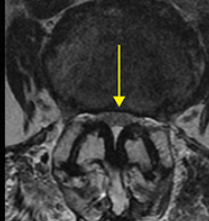

우리 몸은 여러 신경조직으로 구성이 되어 있고 신경 조직들은 뇌에서 시작해서 척추관을 지나 몸의 모든 부분으로 이어지게 되는데요. 척추협착증은 척추관이 다양한 원인에 의해서 좁아져 신경을 누르면서 통증을 동반한 유착과 염증을 일으키게 되는 증상입니다.

척추협착증 진단, CT와 MRI 촬영 등을 통해서 척추관 크기와 주변 관절과 인대, 추간판의 상태를 알아보고 종합적으로 진단을 하게 됩니다. 근전도 검사와 신경전도 검사도 함께 병행해서 하게 되겠습니다.